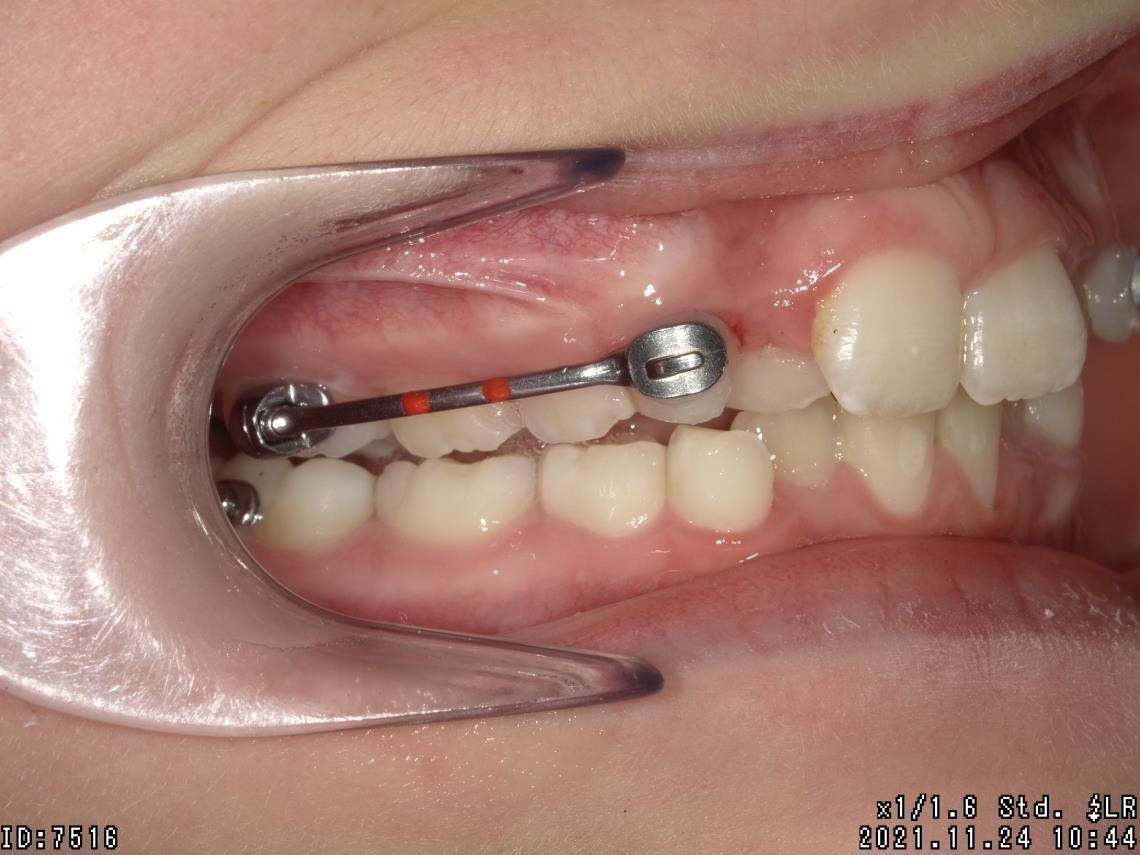

LES BAGUES

Cet appareil dentaire fixe est composé de brackets ou bagues, sortes de petits boutons en métal, en plastique ou en céramique, collés sur les dents et reliés par un fil. Il permet de déplacer les dents du patient dans la direction optimale, de les réaligner au fur et à mesure, de traiter des cas complexes de manque de place et des dents retenues ou dystopiques. Le traitement est moins tributaire de la coopération du patient.